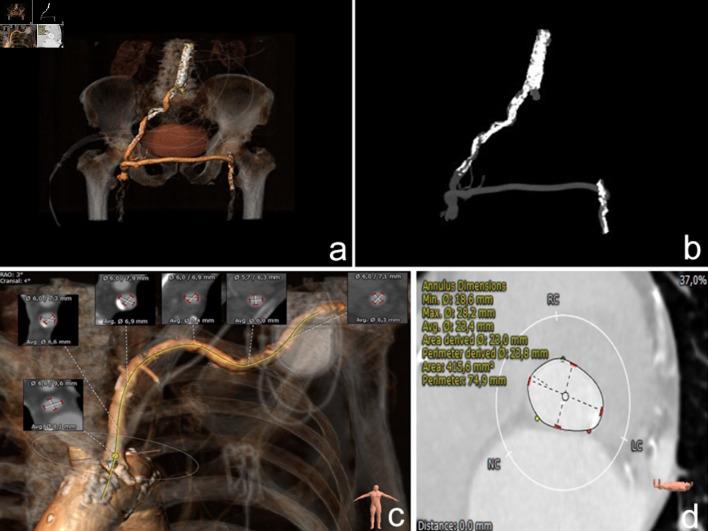

Transfemoral access has been established as the gold standard approach for the majority of patients undergoing transcatheter aortic valve implantation (TAVI). However, in cases with anatomical difficulties or severely diffused peripheral arterial disease, alternative vascular access may be considered such as the transaxillary approach. We present the case of a 92-year-old gentleman with exertional dyspnea due to severe symptomatic aortic stenosis and a history of peripheral femoro-femoral bypass surgery, coronary arterial bypass surgery and a permanent dual-chamber left-side implanted pacemaker. Due to the high surgical risk and the severe anatomical difficulties, the method of TAVI using the left axillary approach was opted. A 14-F vascular sheath was inserted with surgical cutdown and with fluoroscopic guidance while small injections of contrast confirmed the non-occlusive position and the patency of the left internal mammary artery (LIMA) graft. A stiff guidewire was used to cross the heavily calcified aortic valve and subsequently was placed into the left ventricle. Balloon aortic valvuloplasty was performed followed by a successful TAVI with no significant aortic regurgitation or paravalvular leak. The patient recuperated uneventfully and was discharged after 72 h. Axillary access for TAVI is a feasible option for high-risk patients with extended peripheral arteriopathy. To our knowledge this is the first case report describing the implantation of a newer type of intra-annular self-expanding valve platform in a nonagenarian patient with severe comorbidities and such a remarkable history of multiple previous interventions in the selected access site. Meticulous upfront strategy planning and efficient collaboration between specialties is of outmost importance in hybrid procedures for favorable clinical outcomes, especially in cases with challenging anatomies.